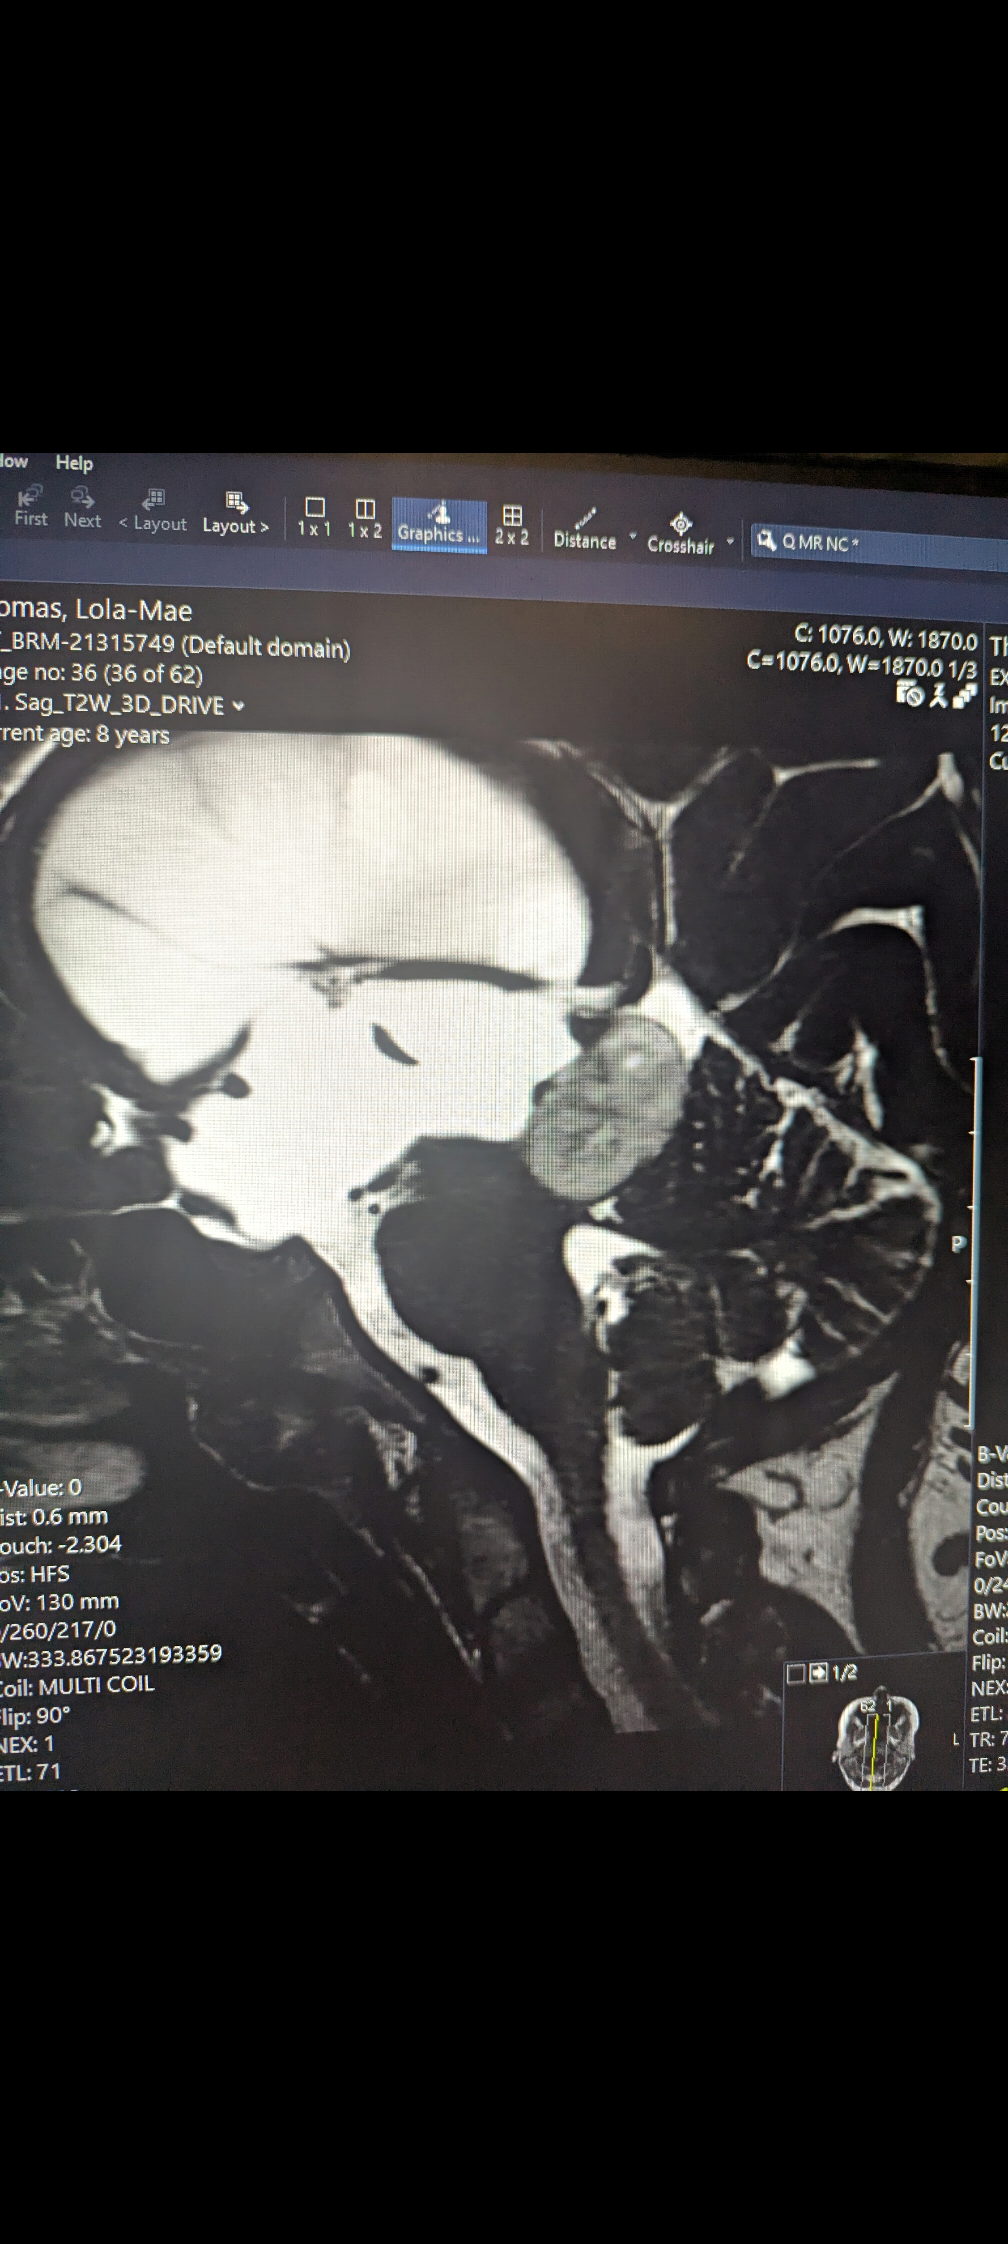

After being referred back to the hospital by the optician who had diagnosed Lola with papilledema (swelling of the optic nerve) Lola had an emergency MRI scan the following day. This revealed Lola had a tumor on the tectal plate of her brain causing a condition called obstructive hydrocephalus (a blockage causing build of cerebral spinal fluid in the brain) this was creating severe intracranial pressure and I was told she would need surgery immediately. We were transferred to great ormand street hospital by ambulance that night.

Once Lola was settled a nurse stayed with her to allow me to have a discussion with a neuro surgeon who expressed to me the severity of lolas condition. She explained that it was by miracle that Lola was walking and talking and that she had not had worse symptoms with her eyesight. When I expressed that she would have been having a scan in 6-8 weeks following referral by our GP the surgeon told me she would not have survived. Lola was extremely lucky that she had not experienced worse and potentially fatal symptoms considering the amount of pressure in her brain (MRI scan showing the amount of CSF build up in brain is in photo gallery) the surgeon talked me through the procedure (Endoscopic third ventriculostomy) they would be performing on Lola the following morning. This procedure was to open the ventricle and allow the fluid to drain and decrease the pressure in Lola's brain. They also would be attempting to take a biopsy of the tumor.

Since recovering and finally starting to get back to some normality, Lola has been having regular scans and her last scan was on the 8th of December at GOSH, we had just been given the keys for our new home and the children were excited to be having Christmas in our new bungalow. While at the new home I was building furniture in preparation to move when I had a scheduled phonecall with Lolas surgeon to discuss her scan results. I was not expecting the conversation that we had. I was told that lolas tumor was progressing and that considering the direction of the growth they will need to operate and remove the tumor. My world fell apart and my sister had to take over the call. The surgeon explained they would need to do a procedure called a maximal safe resection where they will decrease the size of the tumor however would not be able to fully remove it because of the location they will not risk causing damage to the vital areas of Lolas brain. He was apologetic in explaining that this is not the behavior they expected from the tumor however this procedure will allow a definitive diagnosis and we will know exactly what kind of tumor it is. Also he explained that the surgery is essential to prevent Lola facing permanent damage or complications due to the tumor growing in a concerning direction. My instant panic was that Lola will be devastated as she already has server anxiety around this and that I was not sure how to tell her. Her surgeon advised that we give her the best Christmas we can and that we will proceed with the surgery in early January. We decided as a family not to inform Lola of the situation until closer to the time and further discussions have taken place, and we know all the answers that Lola will likely seek.